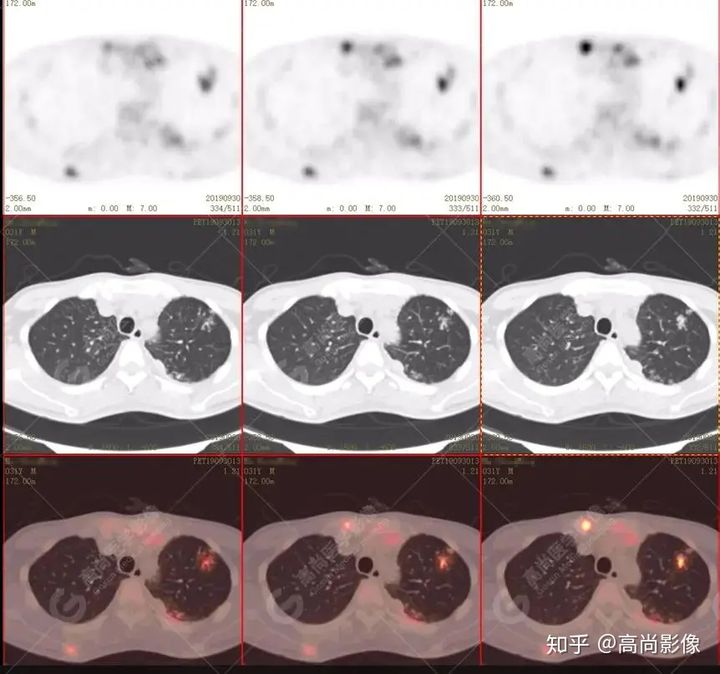

左肺上葉尖后段及下葉背段多發(fā)簇狀斑點(diǎn)狀高代謝灶

左側(cè)胸膜結(jié)節(jié)樣增厚,代謝不同程度增高

好發(fā)上葉尖后段及下葉背段(血氧飽和度豐富);

包括滲出、增殖、空洞、結(jié)核球及纖維化、鈣化等。

本例肺內(nèi)及肺外結(jié)核,尤其脊柱結(jié)核需與轉(zhuǎn)移瘤等惡性腫瘤鑒別,18F-FDGPET/CT檢查有助于臨床排除診斷,而且可以顯示受累臟器范圍以及淋巴結(jié)分布情況。